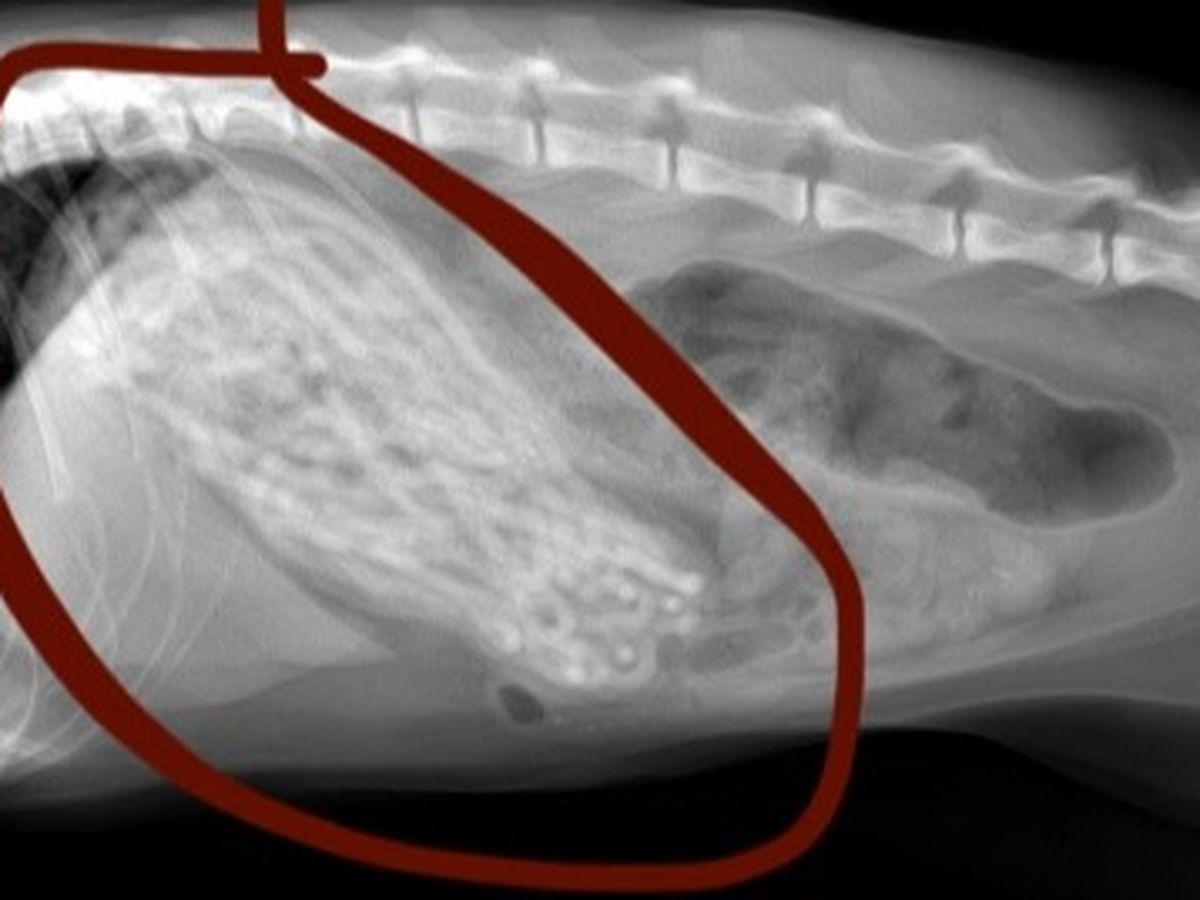

Recently, I noticed that Luna had been eating far less and vomiting for the past week and a half or so, but I was alarmed today (January 5, 2022) when I saw that she had vomited up half of a hair tie. Naturally, I immediately took her to the vet where they did a body exam and some scans. When they showed me the X-Rays (attached in photos), my heart immediately dropped. Luna's stomach was completely filled with black hair ties - the vet expressed that her stomach was so expanded that it would be surprising to him if she could fit anything else in there.

Luna requires an emergency surgery operation (gastrostomy) which they will be performing tomorrow (January 6th, 2022) where they will be opening her stomach to empty the contents and remove the hair ties that are stuck in her stomach. Luckily, the vet told me that these operations are relatively low risk, but her case is unusual in the extent to which her stomach is full, and complications are always possible. Assuming the operation goes well, they will keep her for another two days in the facility to monitor her and ensure she is recovering well.